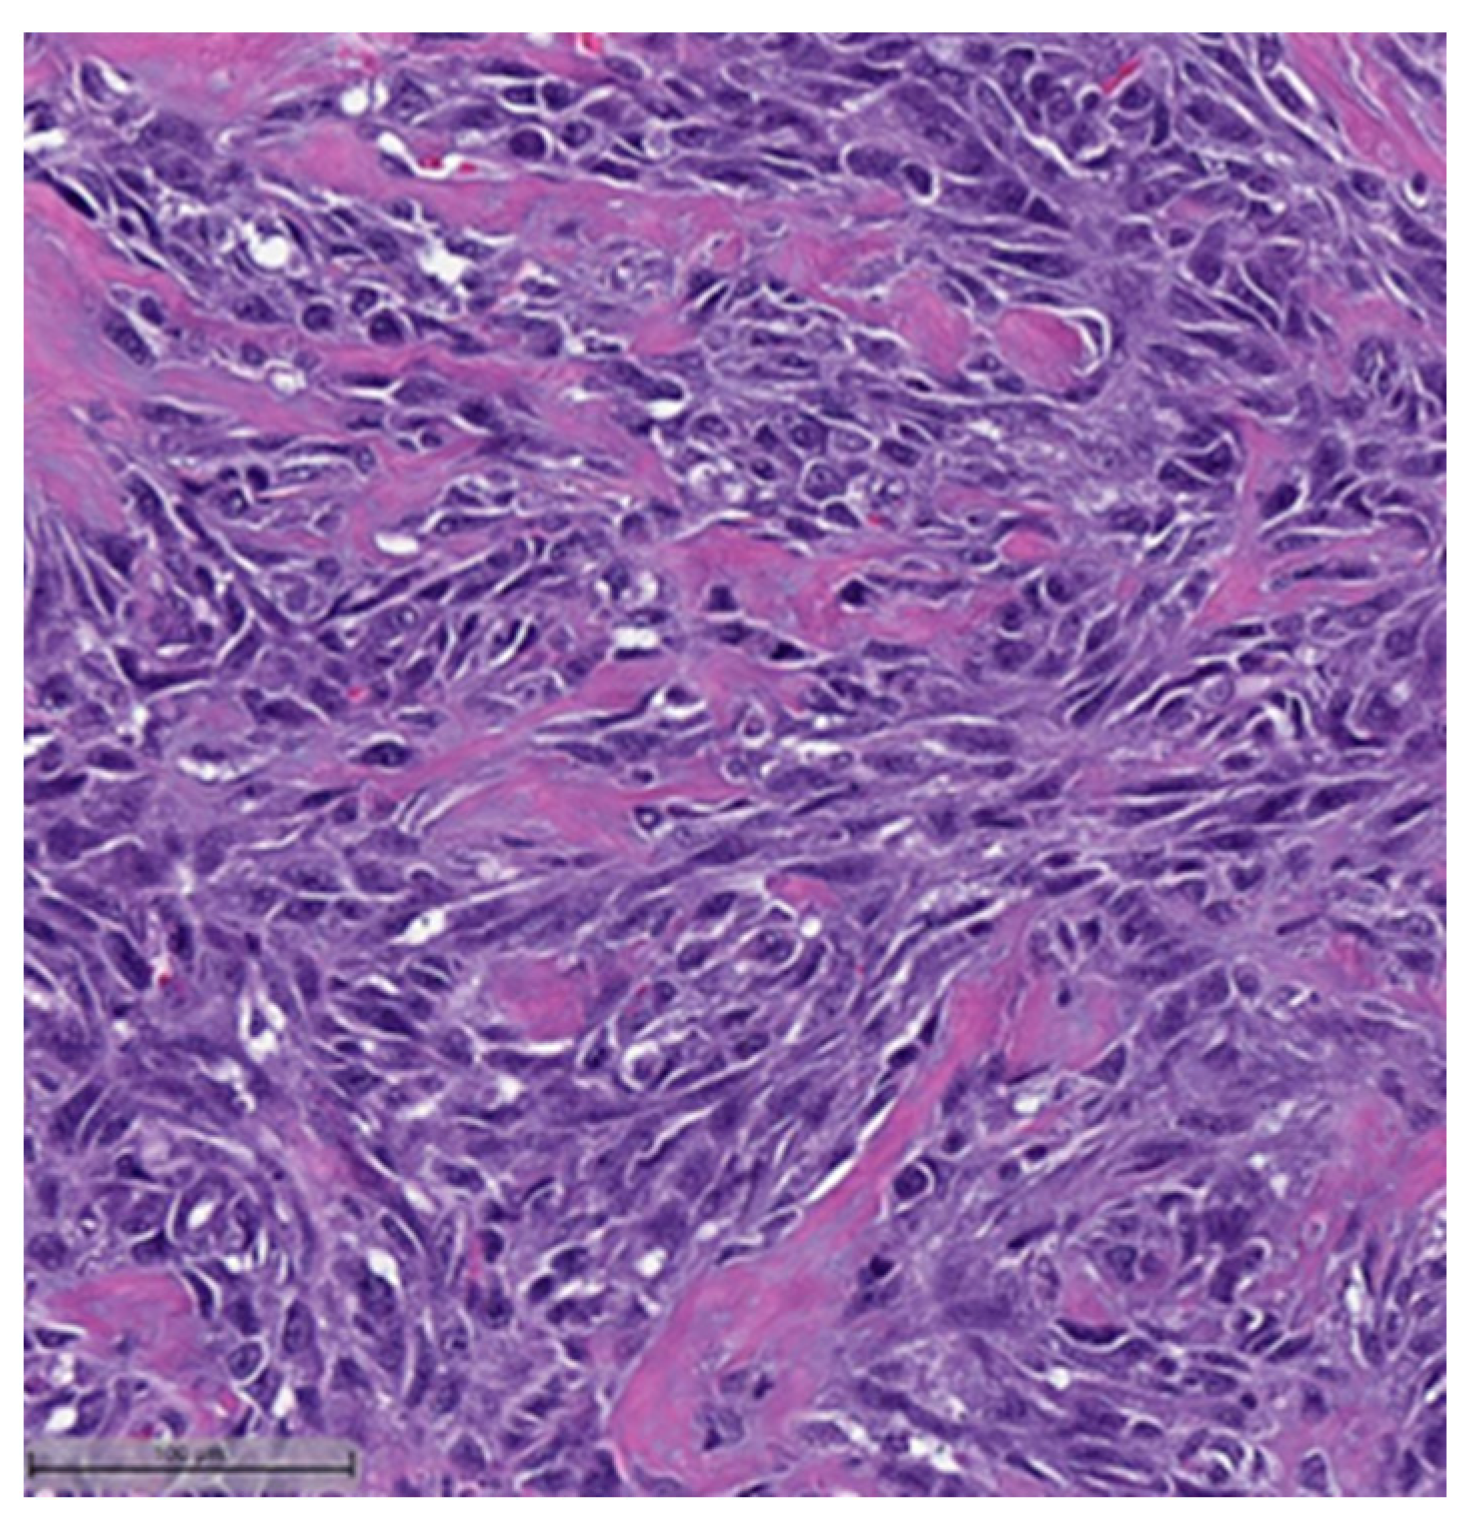

Figure 6.

Metaplastic breast carcinoma with matrix-producing component (H&E, 20×).